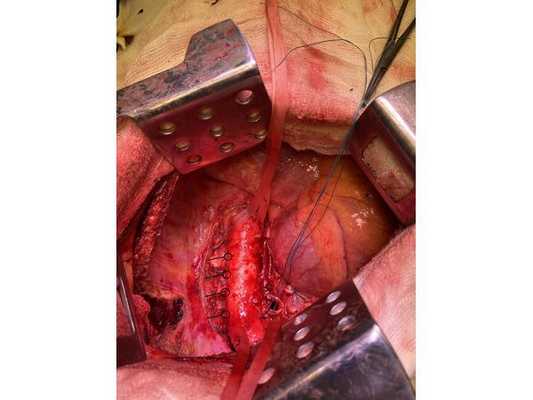

Интраоперационное фото: клипированные межрёберные артерии; аорта на тесёмочных держалках по краям зоны резекции адвентиции; культя главного бронха с провизорными швами при ушивании по Оверхольту

4. Острым путём отсечён левый главный бронх, при этом обнаружено, что опухоль распространяется перибронхиально. Культя левого главного бронха реампутирована (ампутирована повторно) в пределах визуально здоровой ткани стенки бронха, до 1,5-2 см от карины трахеи (гребня хряща между разделением двух главных бронхов). Центральная часть культи левого главного бронха ушита по Оверхольту.

5. Отступив по грудной стенке от края врастания опухоли в аорты на 2 см, рассечена и отсепарована (отделена хирургически) париетальная плевра и адвентиция аорты. Аорта мобилизована по типу "ручки чемодана" и взята на тесёмочные держалки выше и ниже места врастания опухоли.

6. Скелетизируя грудную стенку и аорту, с перевязкой левых межрёберных артерий, на участке рёбер 4, 5, 6 и 7 выполнена полуциркулярная резекция адвентиции аорты, мягких тканей грудной стенки с париетальной плеврой и тканей средостения.